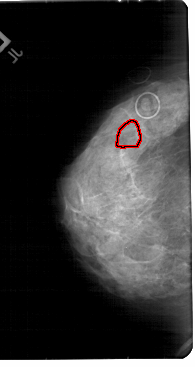

A_1852_1.LEFT_CC

LEFT_CC LINES 5491 PIXELS_PER_LINE 2911 BITS_PER_PIXEL 12 RESOLUTION 43.5 OVERLAY

FILE: A_1852_1.LEFT_CC.OVERLAY

TOTAL_ABNORMALITIES 1

ABNORMALITY 1

LESION_TYPE CALCIFICATION TYPE PUNCTATE DISTRIBUTION CLUSTERED

ASSESSMENT 4

SUBTLETY 2

PATHOLOGY MALIGNANT

TOTAL_OUTLINES 1

BOUNDARY